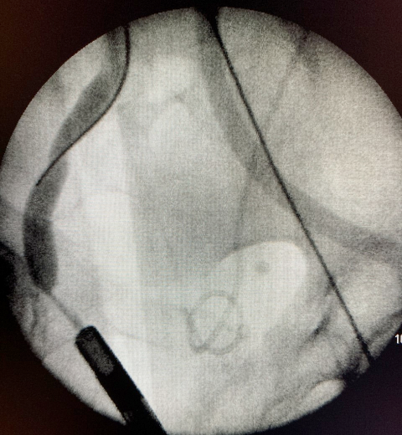

- Duplo J anterógrado Esquerda

- Troca do duplo J à esquerda e passagem anterógrada à direita